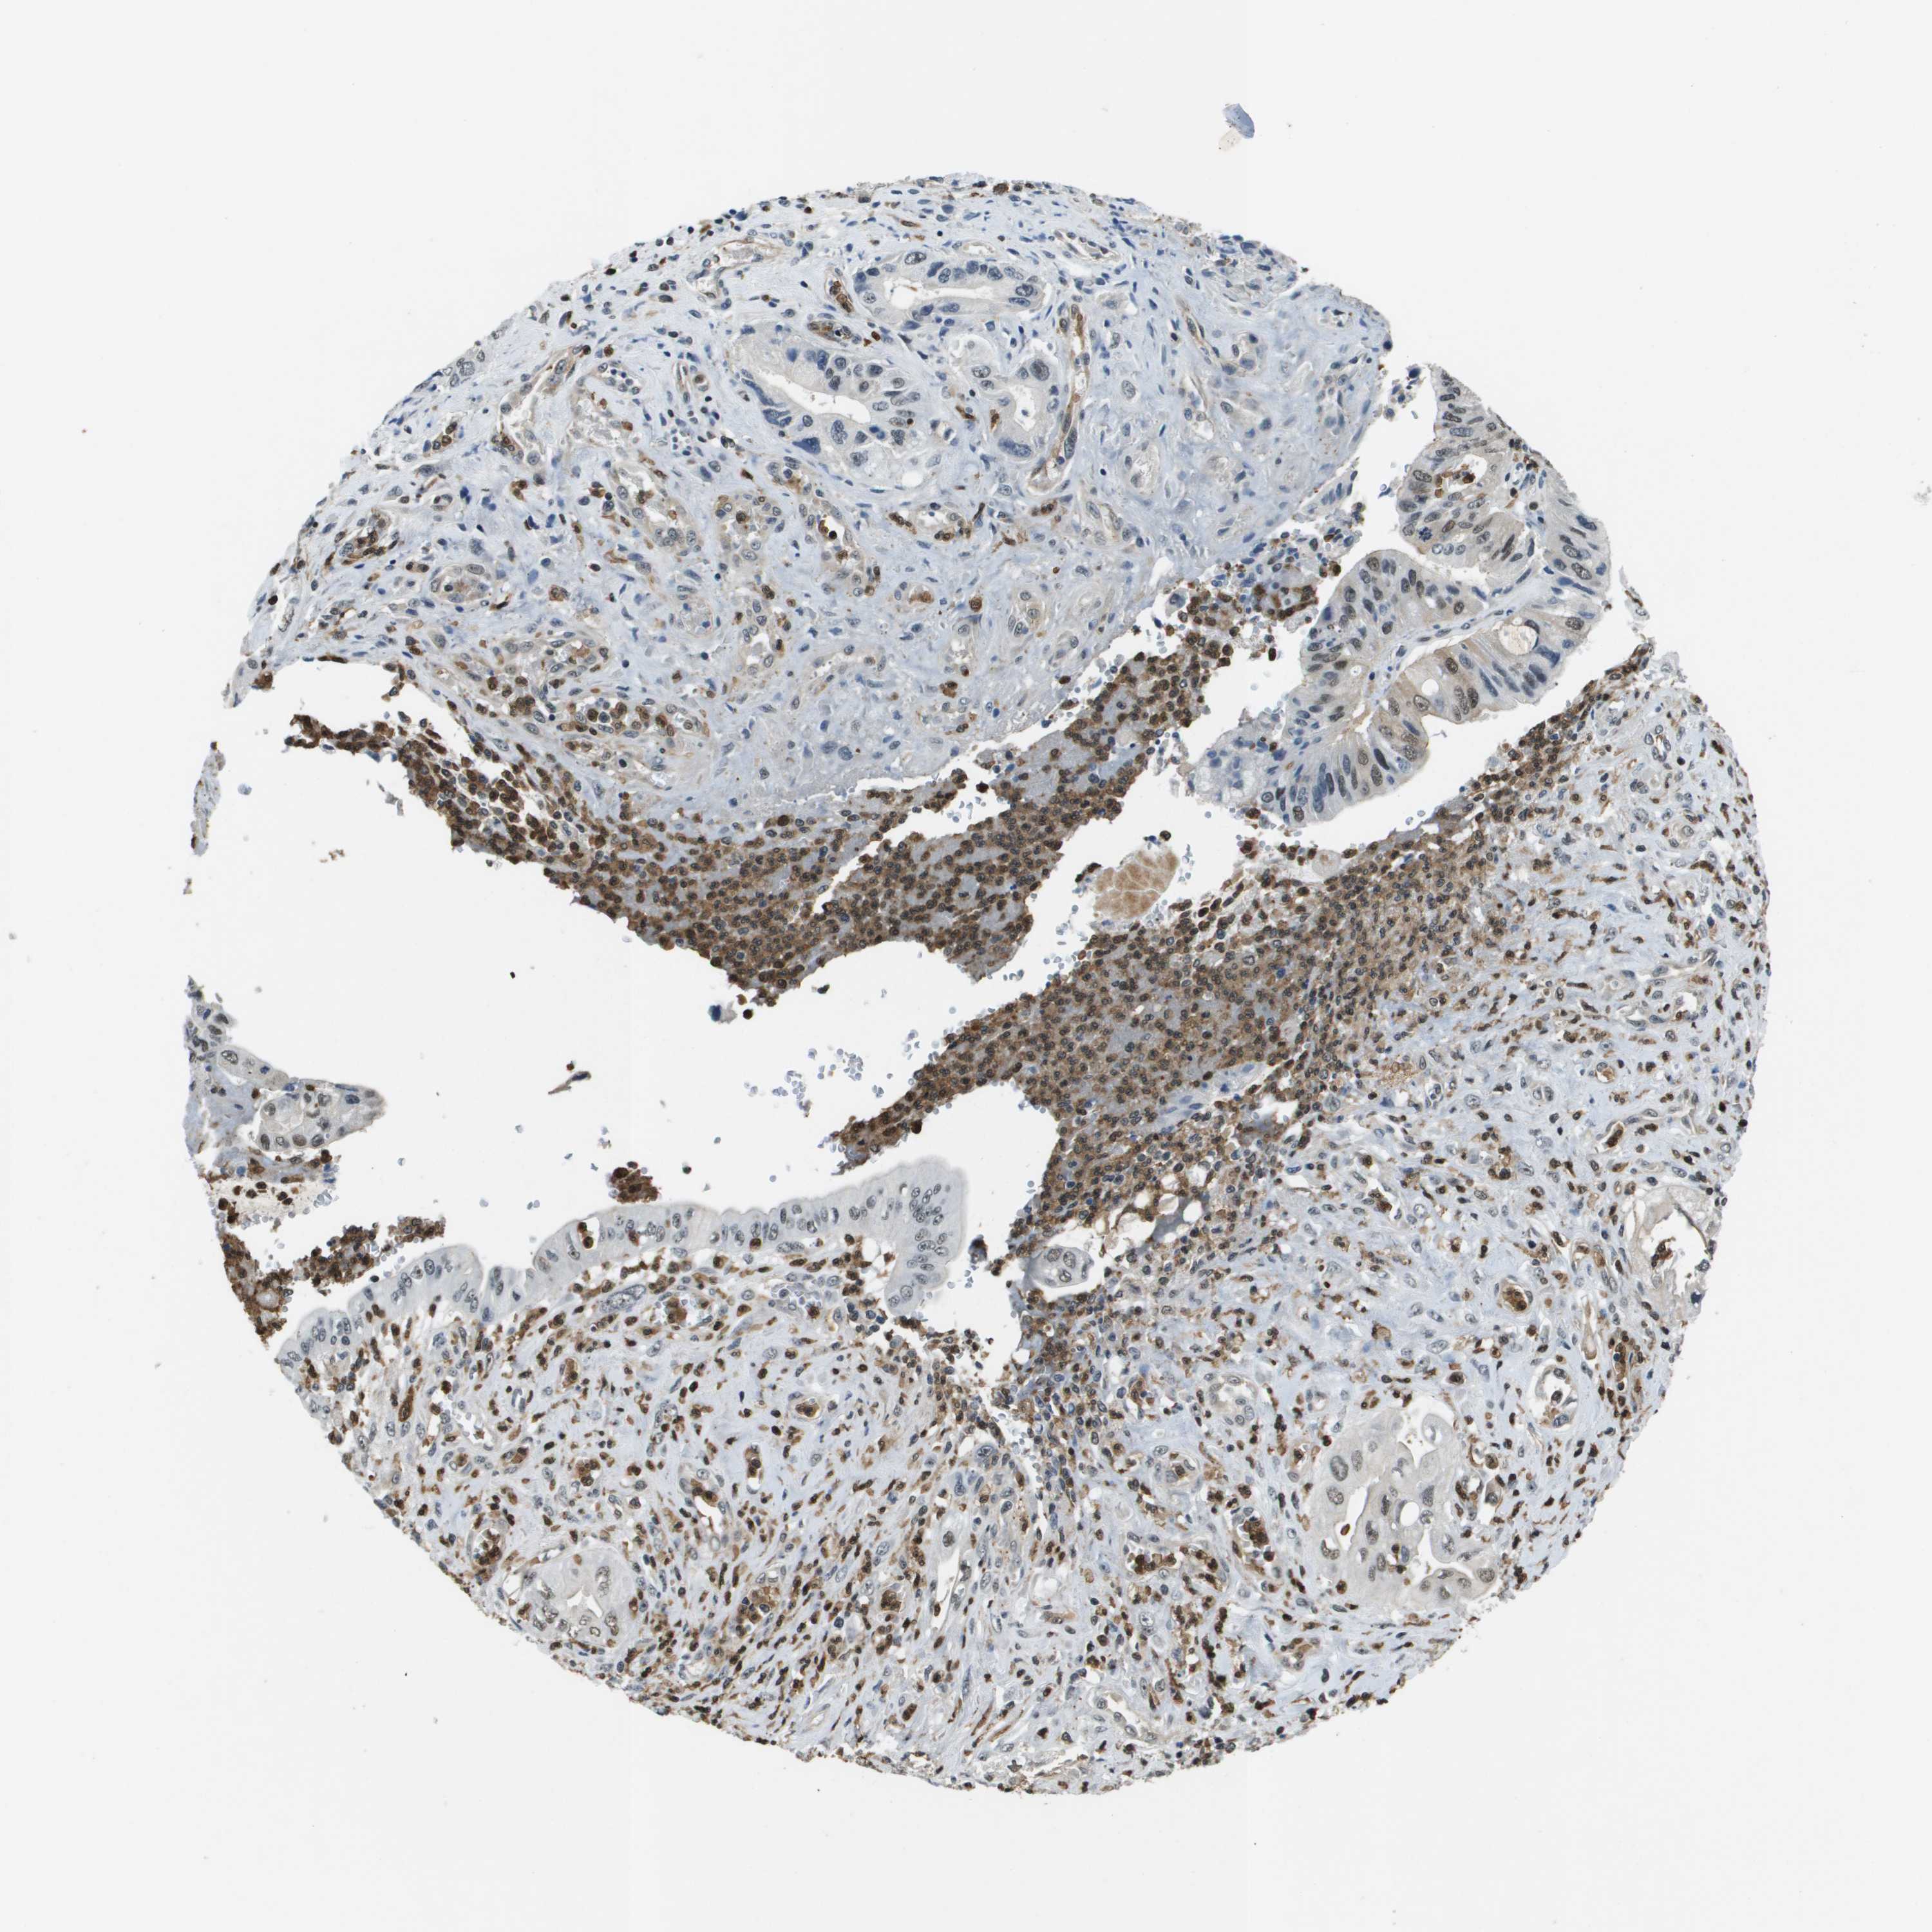

PANCREATIC CANCER - Protein expressioni

A mouse-over function shows sample information and annotation data. Click on an image to view it in a full screen mode. Samples can be filtered based on level of antibody staining by selecting one or several of the following categories: high, medium, low and not detected. The assay and annotation is described here.

Note that samples used for immunohistochemistry by the Human Protein Atlas do not correspond to samples in the TCGA dataset.

Antibody stainingi

Antibody staining in the annotated cell types in the current human tissue is reported as not detected, low, medium, or high, based on conventional immunohistochemistry profiling in selected tissues. This score is based on the combination of the staining intensity and fraction of stained cells.

Each image is clickable and will lead to virtual microscopy that enables deeper exploration of all samples and also displays staining intensity scores, fraction scores and subcellular localization as well as patient and tissue information for each sample.

Antibody HPA016704

Staining

High

Medium

Low

Not detected

Intensity

Strong

Moderate

Weak

Negative

Quantity

>75%

75%-25%

<25%

None

Location

Nuclear

Cytoplasmic/membranous

Cytoplasmic/membranous,nuclear

Adenocarcinoma, NOS